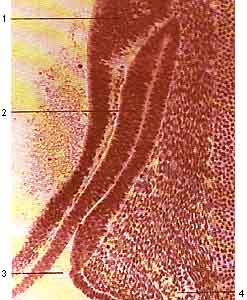

Слева, сагитальный разрез стомодеума и кармана Ратке. Зародыш длиной 10 мм. Сагитальный разрез.

1 - утолщение стенки диэнцефалона - зачаток будущей задней доли гипофиза; 2 - карман Ратке; 3 - область перекреста зрительного нерва; 4 - recessus opticus; 5 - зачаток нижней губы; 6 - a. basilaris; 7 - задний мозг.

Справа, кармен Ратке и зачаток задней доли гипофиза. Зародыш 10 мм. Сагитальный разрез

1- утолщение стенки диэнцефалона, зачаток задней доли гипофиза; 2 - карман Ратке ( его передняя стенка, в дальнейшем даст перреднюю долю гипофиза); 3 - отверстие кармана Ратке.